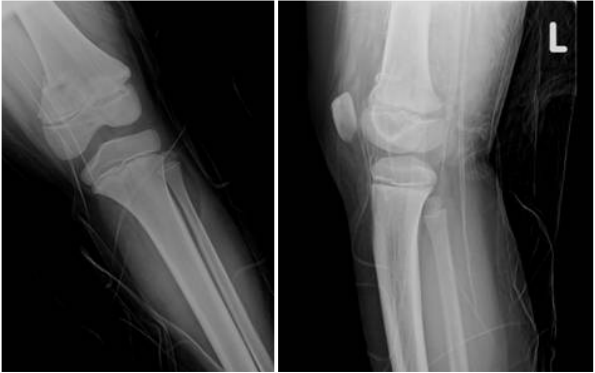

74.20歲男性,因右膝受傷接受X光攝影。附圖為X光攝影影像,最可能的診斷為何?

(A)fibrous dysplasia(B)hereditary multiple exostoses(C)osteogenic sarcoma(D)eosinophilic granuloma